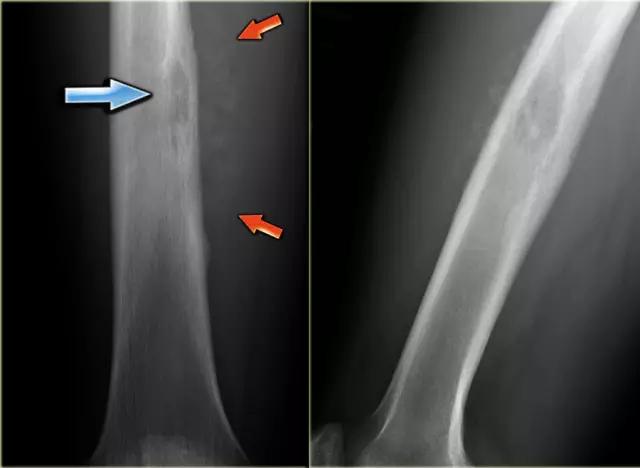

在股骨的骨干的尤因氏肉瘤。注意边界欠清(蓝色箭头)和骨膜反应(红色箭头)。

上图是年轻患者股骨中不明确的溶解性病变。存在具有不规则皮层破坏的渗透性破坏形态。有一个侵略性骨膜反应(箭头)。